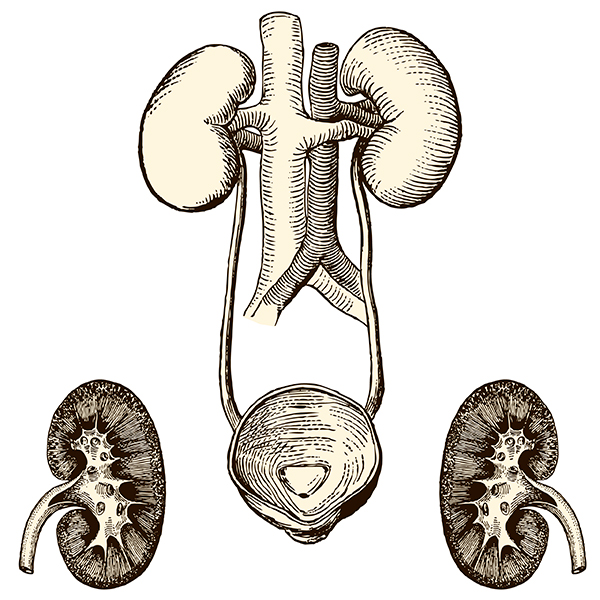

Строение почек человека: Фото и описание